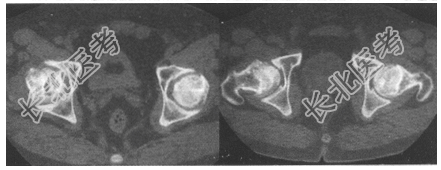

- [材料题] 患者,男,42岁。每日大量饮酒多年,近期觉双侧髋关节疼痛,并放射痛。

- 简答题2、CT片如下图所示,最有可能的诊断是什么?